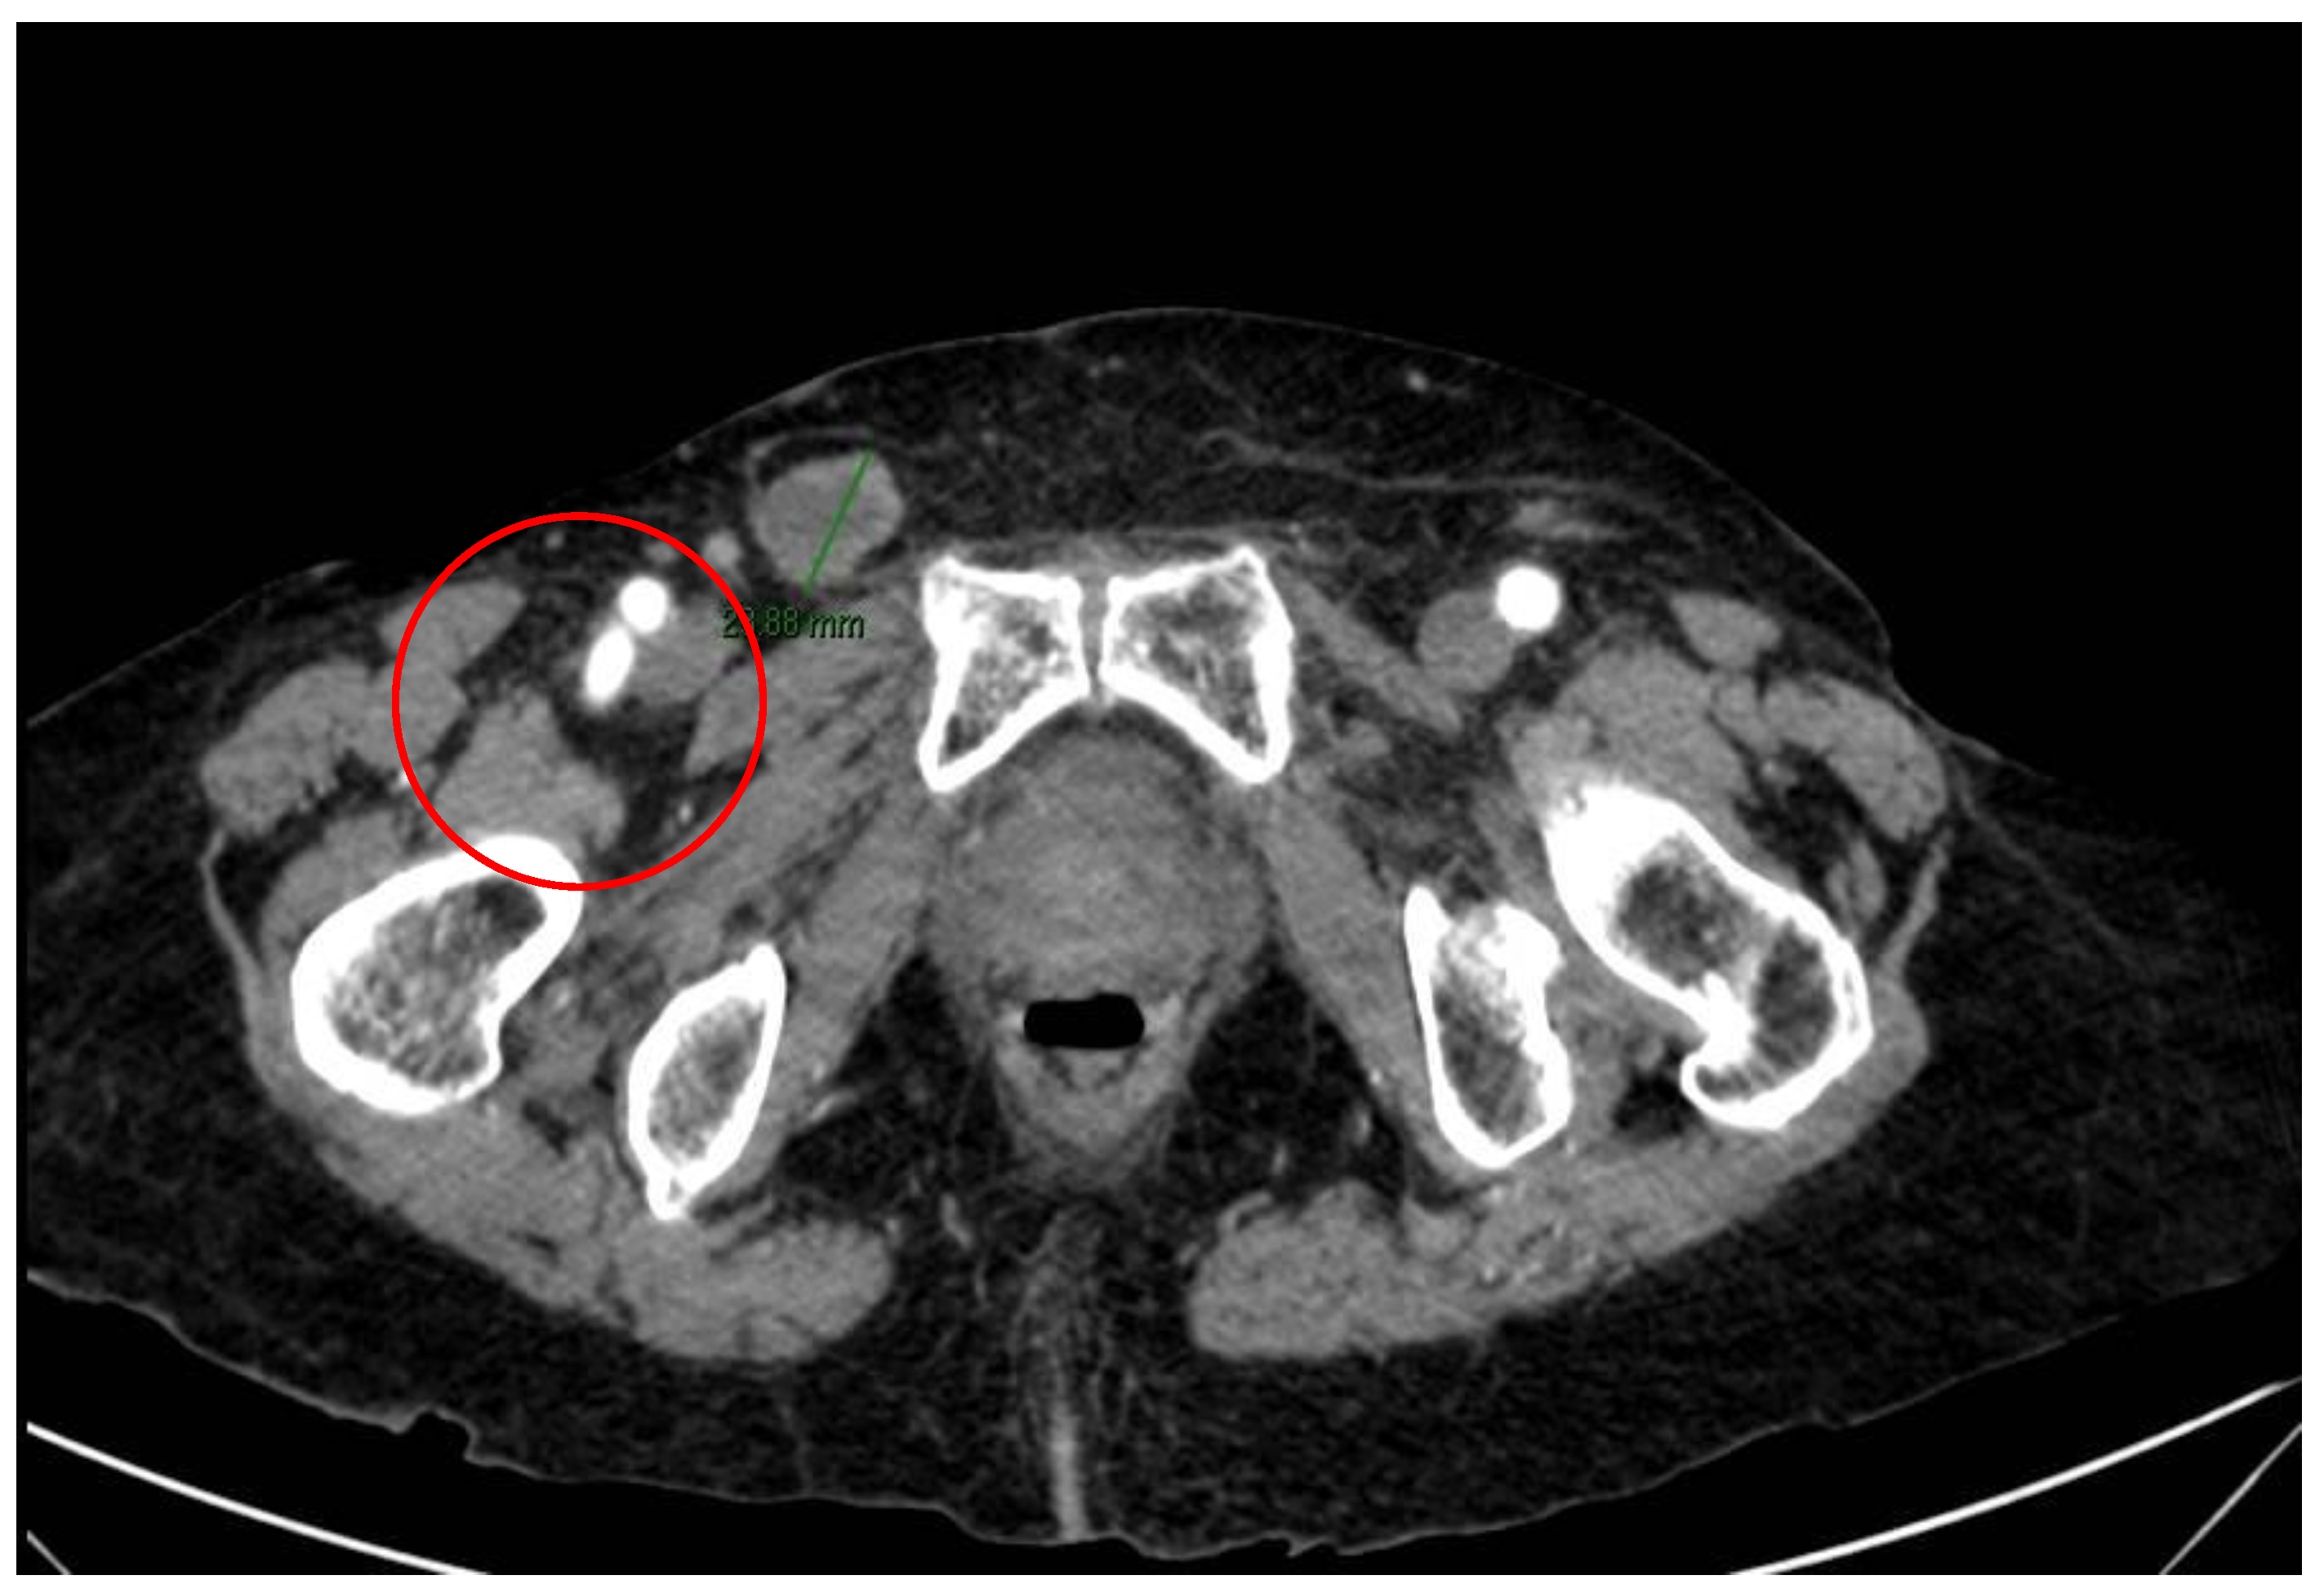

2. Case Report and Evolution

| Our case | F/88 | Squamous cell carcinoma of uterine cervix | 20 | Abdominal pain, vomiting, intestinal obstruction | Resection |